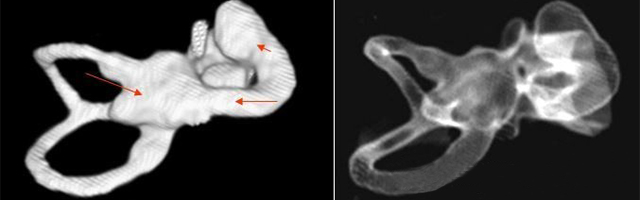

主要根据听力学表现和影像学检查。通过高分辨CT可看到耳蜗畸形。内耳MRI显示膜迷路内水充盈,耳蜗扁平,耳蜗第二圈与顶圈间隔缺损,以及半规管、前庭的畸形。

先天性耳蜗畸形伴前庭和外半规管发育不良